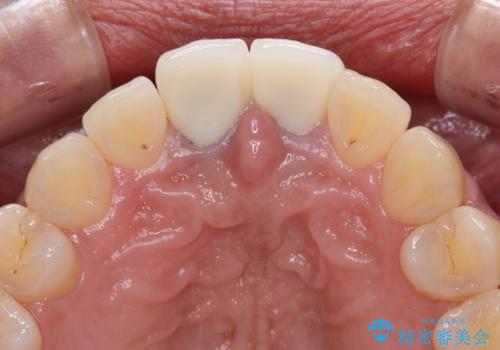

- 前歯のクラウン付近の歯肉が黒く見えることを気にして来院された患者様です。

10年以上前に根管治療を行っており、その際にはラバーダムを使用してしっかりと治療を行っていたとのことで、今回は根管治療は行わずに土台のみを作り替えた上で、オールセラミッククラウンにて補綴治療を行うこととしました。